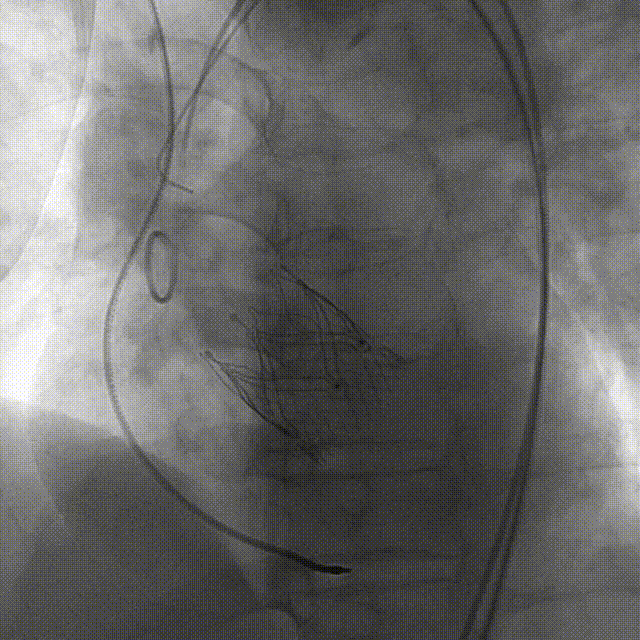

手术过程:5A 标准化流程SOP

术前右窦中心造影

大鞘植入

瓣膜调弯解离

定位键窦对齐验证

定位键入窦验证

深度检查

一键释放

后扩后造影